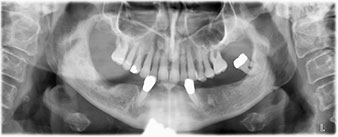

La paciente de 64 años se presentó con una dentición residual compuesta por las piezas dentales 38, 33 y 43 en el maxilar inferior y con una prótesis temporal fijada con ganchos en el maxilar inferior (figs. 1 y 2).